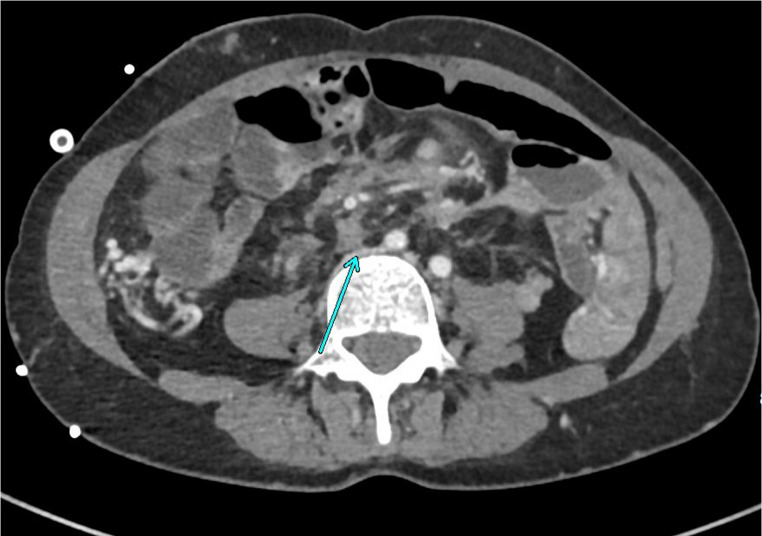

In patients with Familial Adenomatous Polyposis (FAP), large desmoid tumors can develop all over the body. However, the most frequent presentation is as large intra-abdominal masses, usually located in the mesentery of the small bowel. From there, they tend to grow and invade both the abdominal wall and/or the retroperitoneal structures. This can cause life-threatening complications such as recurrent abdominal sepsis with fistulation and damage to vital organs. In selected patients, the only option may be radical resection and replacement by intestinal transplantation (ITx). We aimed to review all the current literature on ITx for FAP-related desmoids and provide an update from the largest single-center experience (2007-2024). All patients undergoing ITx for FAP-related desmoid were included. Between 2007 and 2024, 166 ITx was performed in 158 patients at Addenbrooke's Hospital, Cambridge, UK. Of these, 20 (12%) were for desmoid associated with FAP (10 modified multivisceral transplants, 8 isolated ITx and 2 liver-containing grafts). The five-year all-cause patient survival was 92%, median follow-up was 4.3 years. As the patients presented with very advanced disease, many technical challenges were faced such as: extensive ureteric involvement, abdominal wall fistulation, management of previously formed ileo-anal pouches and extra-abdominal recurrences. Graft selection was another evolving issue, as foregut resection- versus sparing techniques require careful preoperative risk stratification due to increased long-term cancer risk in FAP patients. For certain patients with advanced FAP/desmoid disease, ITx can allow for a radical resection with excellent survival and functional outcomes. However, there is a high degree of initial morbidity associated with the operation and patients should be appropriately counselled. Graft selection and degree of native organ resection requires a careful balanced discussion.

Abstract Image